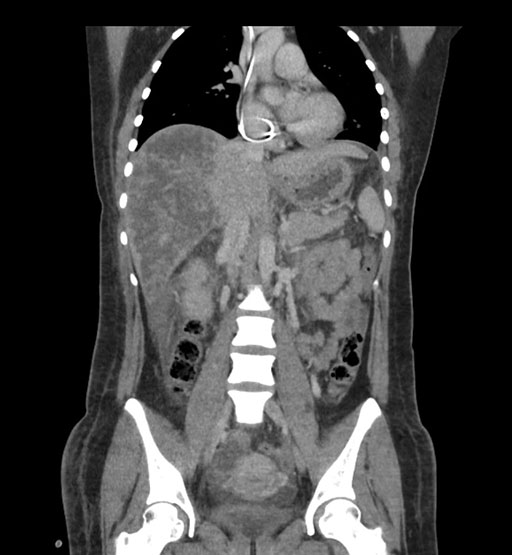

Coronal Arterial

Imaging analysis

Based on initial findings, which issue(s) would you be most concerned about?